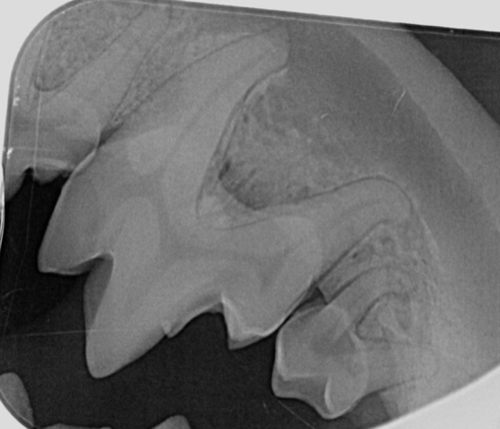

Images

Vous pouvez télécharger les images ci-dessous en cliquant dessus.